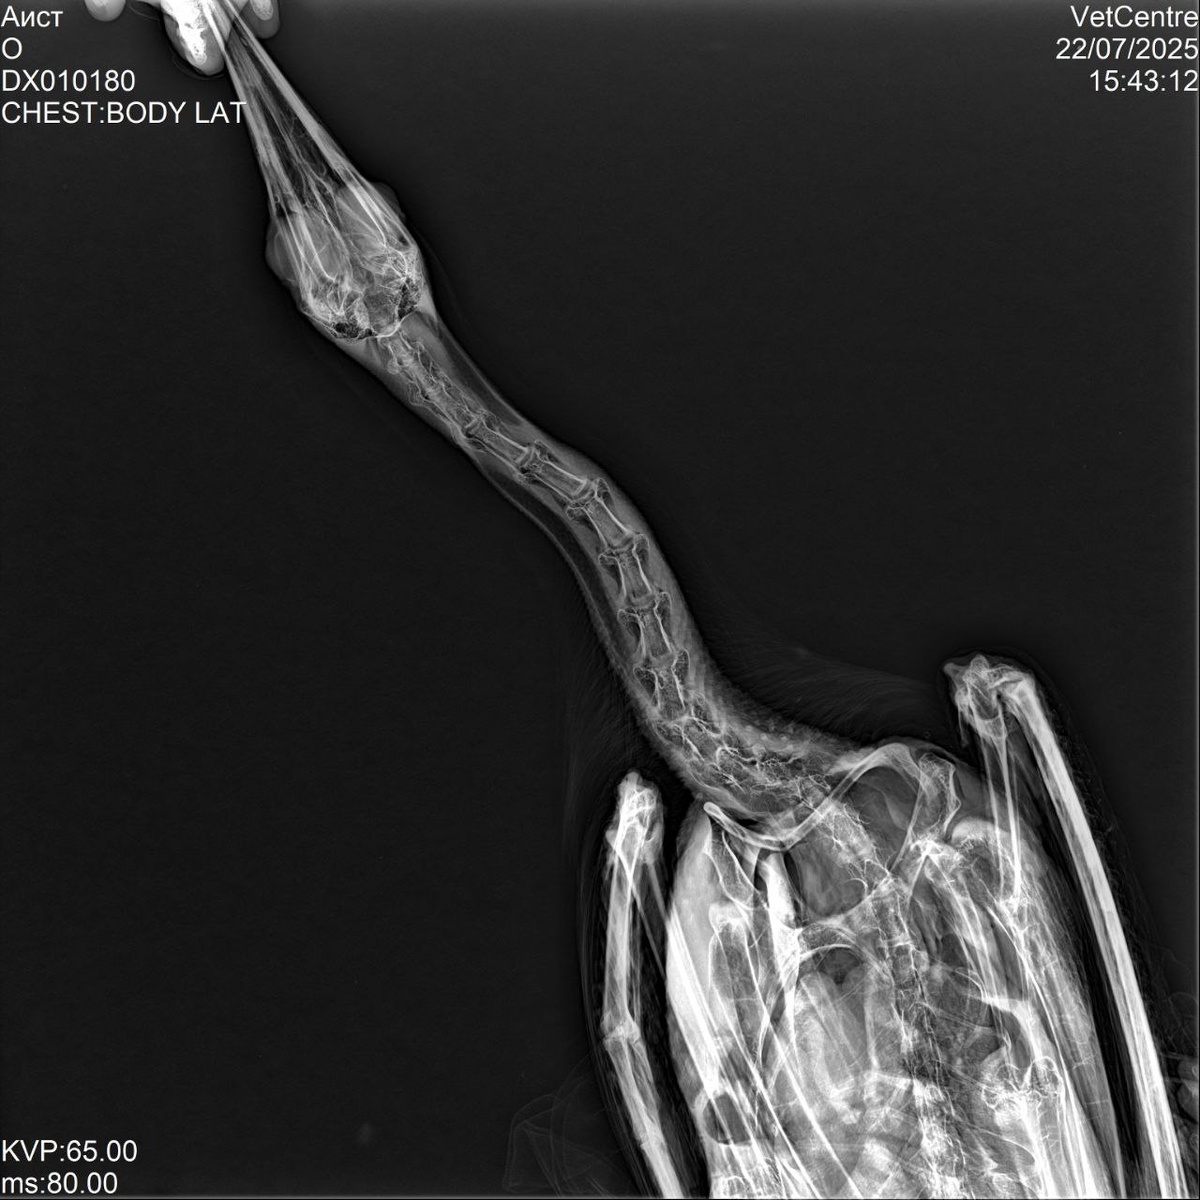

Рентген Аистенка Иваныча, травм нет, в остальном по состоянию завтра должно быть все понятно, если наши подозрения подтвердятся, то завтра он должен будет голову держать, держим за наши надежды кулачки! Дело в том, что сегодня после утреннего кормления, он срыгнул чернозеленую субстанцию вместе со съеденной рыбой, мы решили больше его не кормить и повезли к врачу, вчерашняя и сегодняшняя порция чиктоника смазала видно застрявшую гадость в пищеводе, эта гадость начала разлагаться и вызвала инфекцию. Если это так, то обильное кормление, ударная доза витаминных добавок и он еще в Африку слетает! Быть Добру!